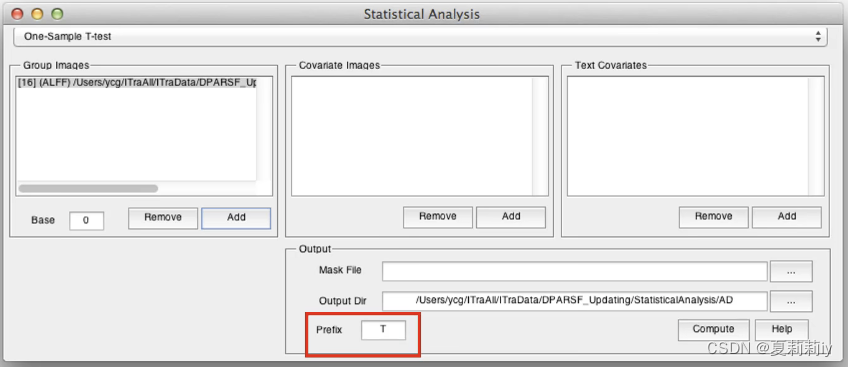

(3)One-Sample T-Test

①可以看看患者和普通人ALFF的图像差异

②在左边栏加入被试,右边是协变量,可以不添加

③生成的结果示例